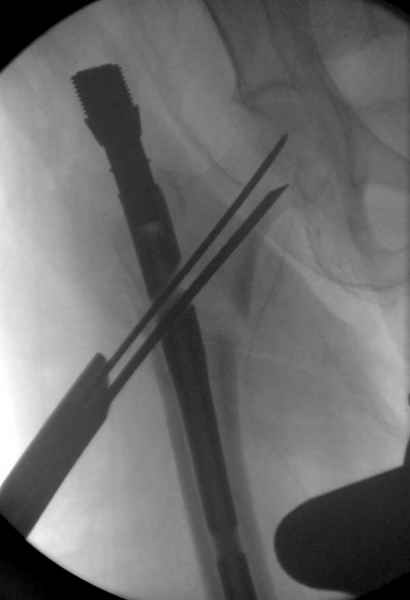

Здесь сканнированные снимки импланта и операционные снимки больной.

На этом снимке процесс компрессии нижним болтом.